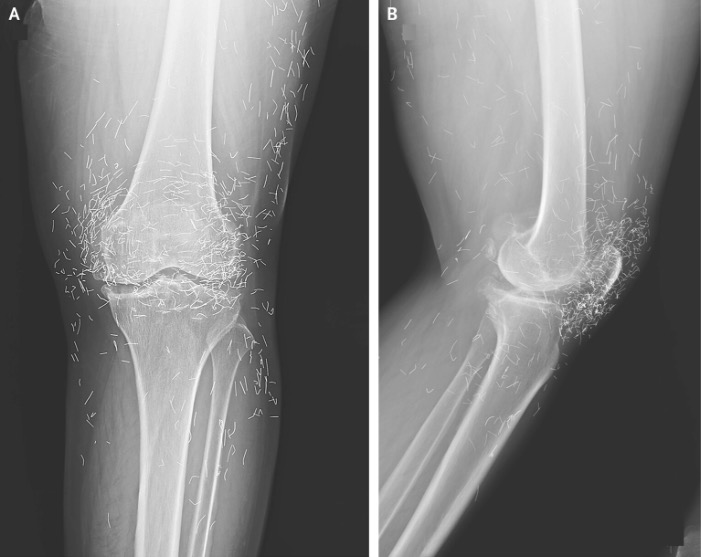

W związku z tym kobieta zdecydowała się na akupunkturę. Zgodnie z tym, jak opisano jej przypadek w czasopiśmie New England Journal of Medicine.

Akupunktura, znana od wieków metoda leczenia alternatywnego, polega na wkłuwaniu igieł w określone punkty ciała w celu złagodzenia bólu lub leczenia chorób. W tym przypadku igły wykonane ze złota, celowo pozostawiono w kolanach pacjentki w celu dalszej stymulacji.

Profesor ostrzegł również, że wbite igły mogą utrudniać odczytanie zdjęć rentgenowskich. „Igły mogą zasłaniać niektóre części anatomiczne” –powiedział Guermazi w 2013 roku.

Co gorsza, igły pozostawione w ciele mogą stwarzać zagrożenie dla przyszłych badań obrazowych. „Pacjent nie może poddać się rezonansowi magnetycznemu, ponieważ igły pozostawione w ciele mogą się przesunąć i uszkodzić tętnicę” – dodał Guermazi.